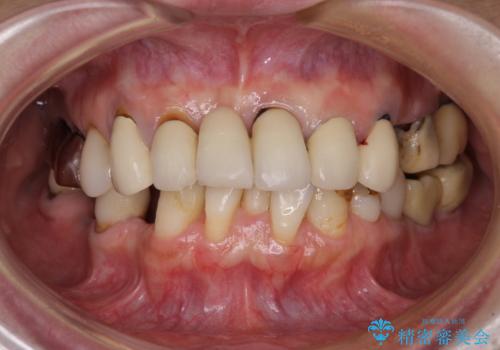

- 以前通院していた医院で、奥歯のインプラント埋入、前歯部のインビザライン矯正を行ったものの、そのまま放置してしまったとのことで来院された患者様です。

下顎前歯や上顎奥歯などをワイヤー装置により部分矯正を行い、歯列を整えた上でインプラン部分を含めてオールセラミッククラウンにて補綴治療を行うこととしました。

ご主人が通院されていたことで、ご紹介により来院されました。

インプラント上の仮歯がボロボロになり、前歯に非常に負担のかかる状態であったため、早急に奥歯の仮歯を修復し、矯正治療、奥歯の補綴治療、前歯の補綴治療と順々に進めて行きました。